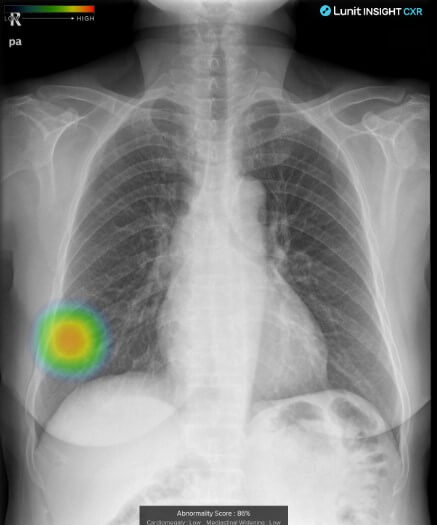

의료AI 대장주 루닛

의료AI 대장주 루닛은 설립 이후 딥러닝 기술 및 AI기술을 통해 인간의 시각적 한계를 보완하는 판독보조 solution을 개발하고 상용화하고 있는 부분이 관심을 받고 있습니다.